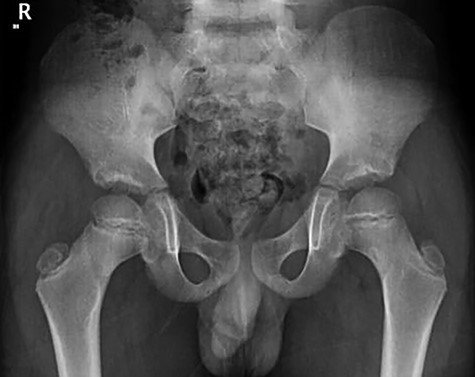

Patient was given adequate analgesia and routine blood tests were done (CRP 5.8 WBC 7.5x109). X-rays revealed small Lytic lesion with surrounding sclerosis at infero-medial aspect of left femoral neck in antero-posterior and lateral views (Fig. 1, 2).

Follow-up of the case showed complete regression of the symptoms. Patient was full weight-bearing and performing daily activities with no pain, straight leg raises up to 90 degrees, Range of motion was fully painless with flexion 120 degrees, while extension, abduction and external rotation were 20, 40 and 35 degrees respectively (Figure 8, 9).

Follow-up X-ray showed regression of the lesion in the form of progression of the dense sclerosis of the defect of the left femur while the right femur neck lesion is barely visible (Figure 10) and advised for watchful waiting.